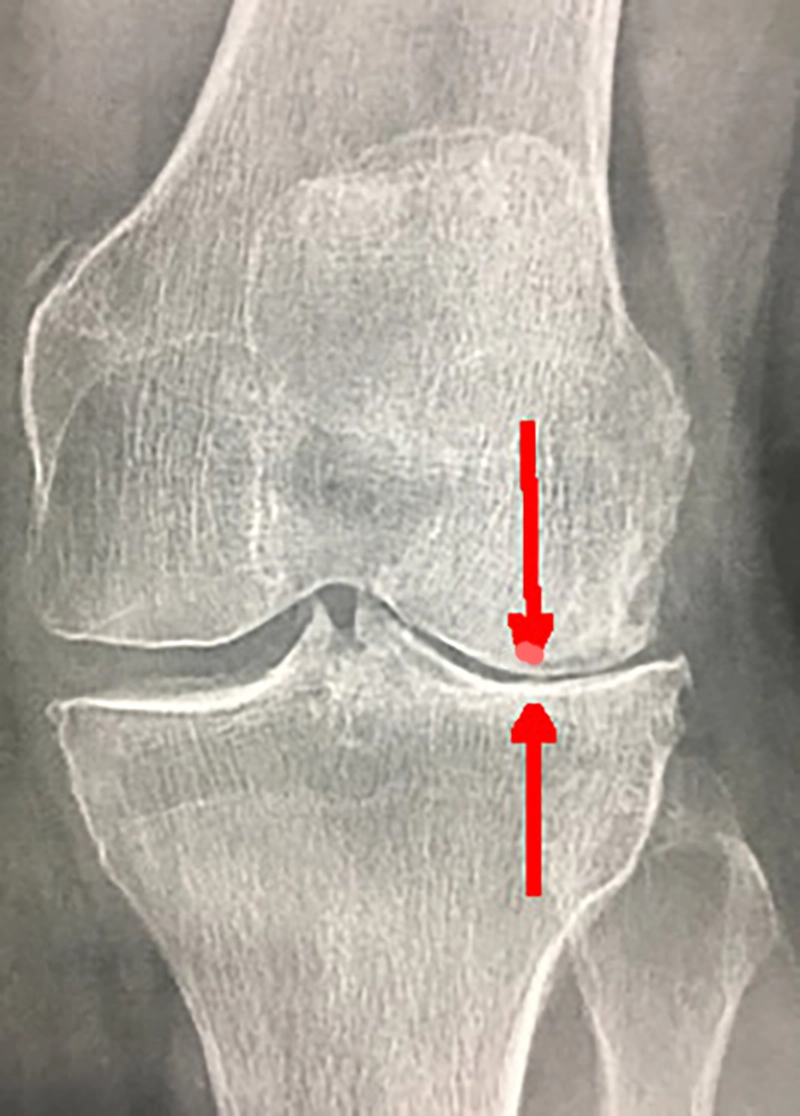

Si la radio de votre genou montre un pincement net, ou la disparition (photo) de l'espace entre le fémur et le tibia (définition de l'arthrose),

Radio d'une arthrose interne du genou droit de face

Sur la radio ci-contre, vous pouvez voir le ciment (gris clair) autour de la tige de la pièce tibiale (flèches rouges).

prothèse totale de genou cimentée au niveau du tibia et avec médaillon rotulien